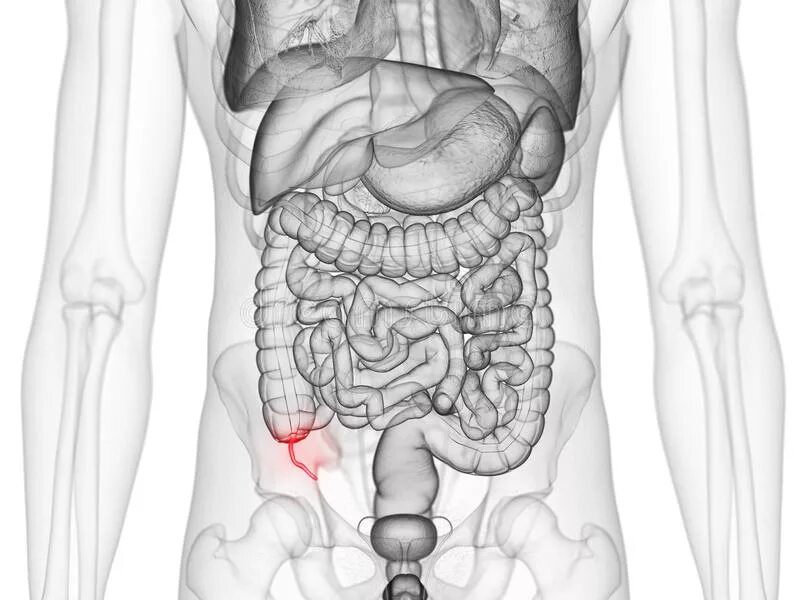

3 обп